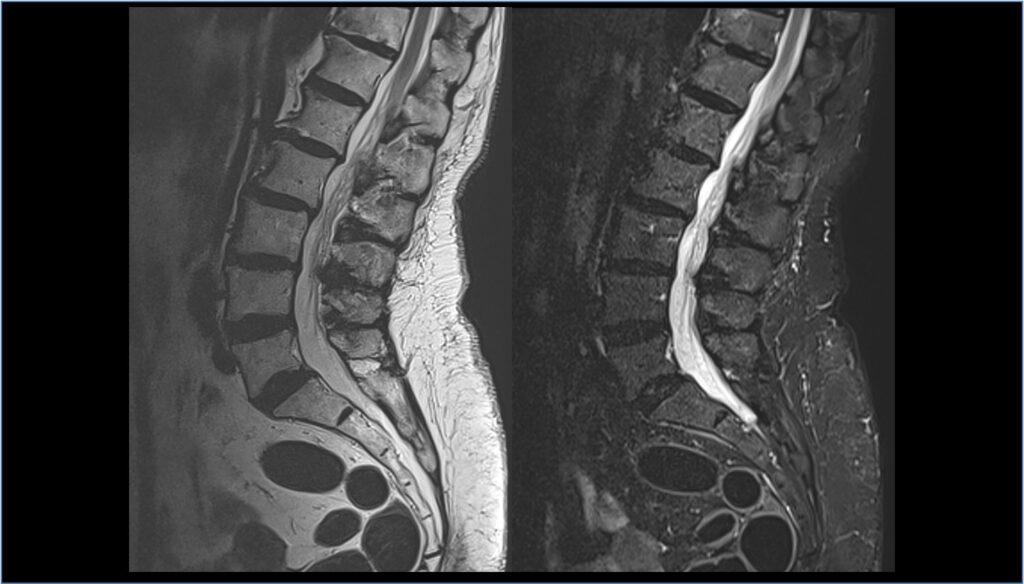

RM rachide o della colonna vertebrale

Cos’è? Le indagini di Risonanza Magnetica della colonna (RM rachide) rappresentano il Gold Standard per la visualizzazione del midollo spinale, delle radici nervose o delle